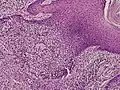

Dermoscopy and histopathology of eccrine poroma: (A) Clinical presentation of a nonpigmented eccrine poroma sensu stricto as a pink nodule located on the foot (B,C) Dermoscopy shows milky red areas (light blue arrow), milky red globules (dark blue triangle), and dotted vessels (black arrow) (original magnifications ×20 and ×40, respectively). (D,E) Histopathologically, the neoplasm consists of poroid and cuticular cells and tubular structures that are continuous with the epidermis (H&E stain, original magnifications ×10 and ×40, respectively).[19]

Microscopic histopathological examinations of the tumor tissues of all poroma variants stained with hematoxylin and eosin dyes reveal: a) basophilic "poroid cells" (i.e. small, cuboid-shaped cells with oval nuclei which resemble cells in the peripheral layer of the distal portion of eccrine sweat gland ducts[20]) that may form cords and broad columns extending downward from the epidermis; b) larger cuticular cells (i.e. squamous epithelial-like eosinophilic cells that resemble the luminal cells lining eccrine sweat gland ducts[20]); and in some cases c) clear cells (i.e. cells with small nuclei surrounded by pale cytoplasm).[3] Poroma tumor tissues may appear highly vascularized and/or have areas of necrosis, i.e. dead or dying cells. Hidroacanthoma simplex variants are mainly composed of poroid cells, few cuticular cells, and no clear cells and are confined to the epidermis; dermal ductal variants are mostly confined to the superficial dermis and are composed of small solid and cystic nodular aggregates of poroid, cuticular, and clear cells; poroid hidradenoma variants have large aggregates of solid and cystic components and extend deeper into the dermis or even subcutis; and eccrine poroma variants are composed of all three cell types but are primarily located in the epidermis and superficial dermis. Poromas may have 2 or more of these variants in the same tumor tissue and the variants typically have histopathology findings that are not clearly distinguishable from each other.[3]